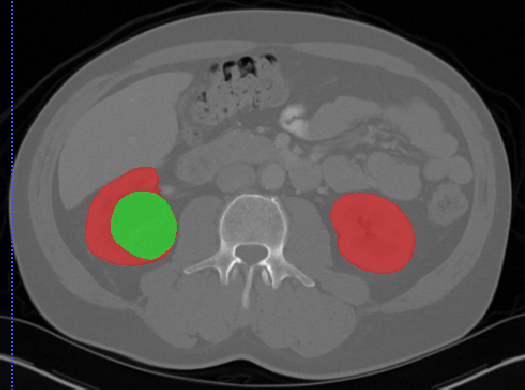

# 肾脏

## Kits19

| [Kits19](https://kits19.grand-challenge.org/) | 肾肿瘤 | 分割 | | | | | |

[Aistudio下载](https://aistudio.baidu.com/aistudio/datasetdetail/24582)